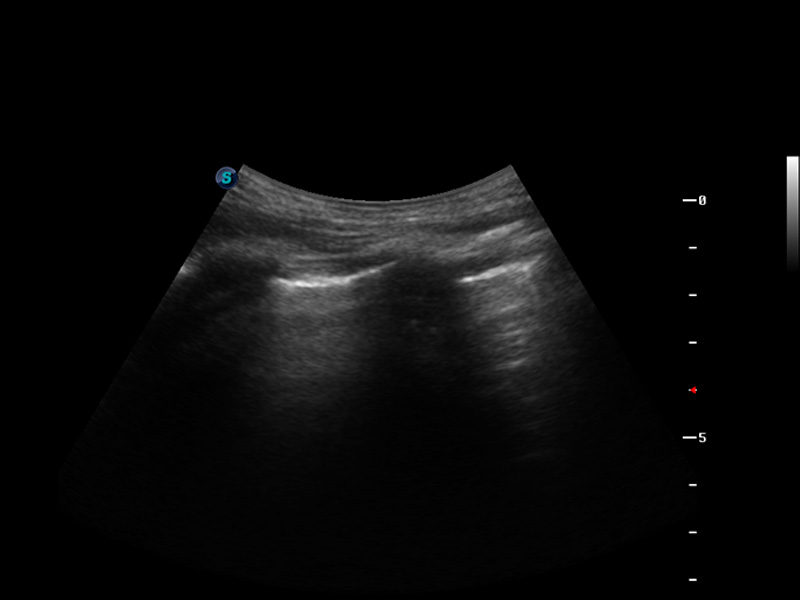

S9便携式彩色多普勒超声诊断仪是哈哈体育官网研发的高端便携彩超设备,外观设计新颖、产品性能卓越。S9在便携超声领域采用了突破传统的触摸屏交互设计,并以先进的软件硬件技术和设计理念,为您带来清晰的图像质量、稳定的工作性能和便捷的操作体验。